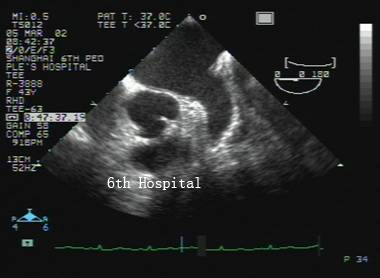

經食道探頭

經食道超聲顯示正常心臟,圖像清晰度高

一般常規的經胸超聲心動圖,檢查時需要通過肋間隙的透聲窗口發射和接收超聲波,為了保證足夠的探查深度,必須使用較低頻率的探頭,圖像分辨力因而受到限制,尤其在肥胖、肺氣腫、胸廓畸形、胸部創傷的患者中,所獲得的超聲圖像質量不高。為此根據臨床需要,對于部分患者,醫生會建議經食管超聲心動圖檢查。經食管超聲心動圖是利用直徑大約1cm的管體將小型的超聲探頭送進食管,近距離觀察心臟和大血管的解剖結構和血流信息。通過這種方法,大大改善了圖像的質量,提高了超聲心動圖的診斷價值。